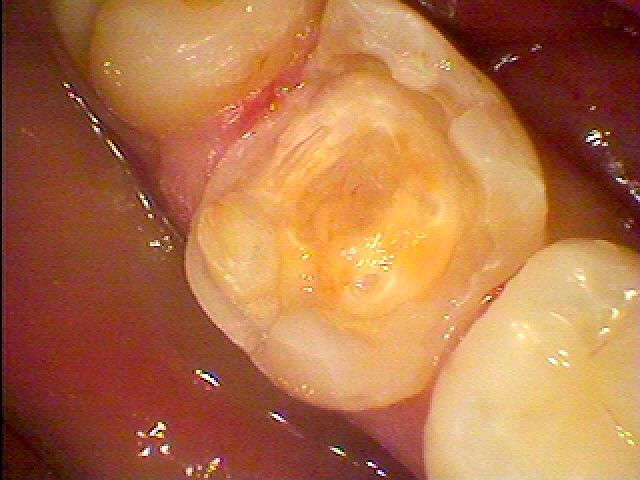

銀歯から白い歯へ 審美治療| |広島市安佐南区の歯科医院 銀歯から白い歯へ 審美治療 トップ お知らせ・ブログ 銀歯から白い歯へ 審美治療 銀歯から白い歯へ 審美治療 Web診療予約 初めての方へ 選ばれ続ける理由 院内設備について 歯が痛いしみる一般歯科 歯がぐらぐらする歯周病 健康な歯を保ちたい予防歯科 子供の虫歯予防をしたい小児歯科 銀歯をセラミックに審美歯科 白い歯を目指しませんか?ホワイトニング 矯正専門医がいるので安心矯正歯科 抜けた歯を補いたいインプラント・入れ歯 医院案内 スタッフ紹介 メリィハウス歯科クリニックオフィシャルホームページ ラベンダー歯科クリニックオフィシャルホームページ お知らせ・ブログ ホーム 診療科目 一般歯科 歯周病治療 予防治療 小児歯科 審美治療 ホワイトニング 矯正歯科 入れ歯・インプラント マウスピース矯正 初めての方へ 院長・スタッフ 設備紹介 医院案内・アクセス メニューを閉じる